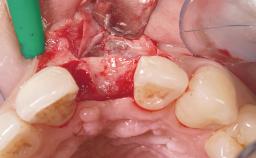

A 33-year-old female patient presented with an upper left central incisor that required extraction after a failed endodontic therapy. The tooth had been traumatized when the patient was a teenager and had undergone several endodontic treatments, including two apicectomy procedures. The patient was in good health and did not smoke. Clinical examination showed that the patient had a high lip line. In full smile, the gingival margins of the upper teeth were visible to the first molars. The gingival margins of central incisors 11 and 21 were only just showing. Examination of tooth 21 confirmed that the tooth was mobile and had hypererupted by 1 mm.

| Placement Protocol | Immediate implant placement |

| Socket Morphology | Single-root socket |

| Socket Integrity | Damage to one or more bone walls |